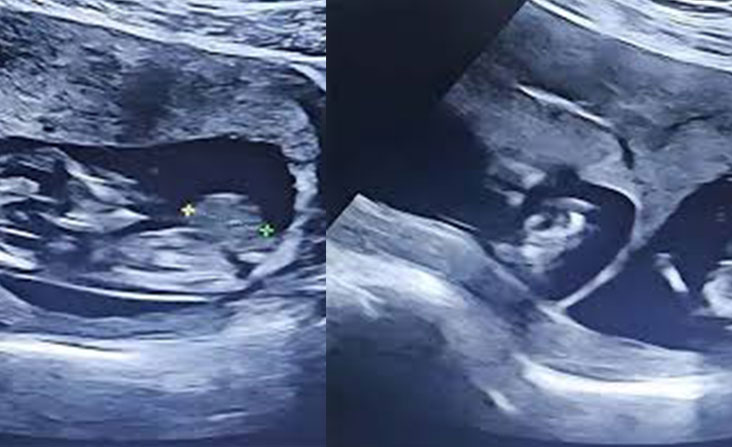

Authors : Sampath Gnanarathne, Ayodhya Kariyawasam Publication date : 2024/8/25 Omphalocele is a rare congenital anomaly with eviscerated abdominal organs in the proximal segment of…